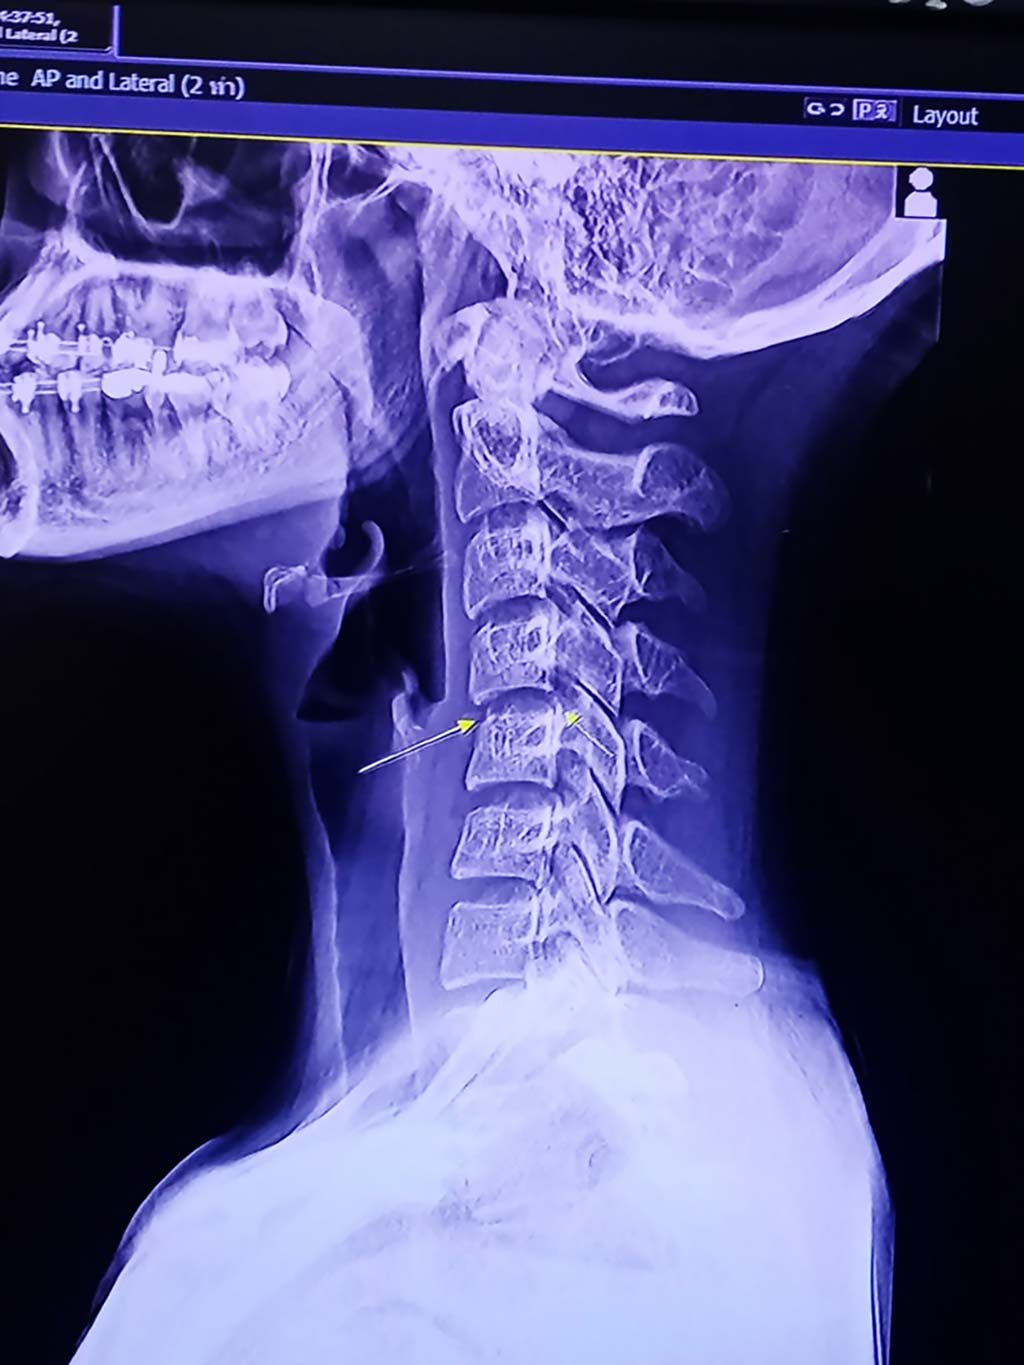

女性は肩に痛みがあったため、首をひねるマッサージを受けたというが、施術後に体のしびれなどが生じる「頚椎症性神経根症」を発症し、亡くなる1週間前は意識不明の状態だったという。また、病院で撮影したX線検査では頚椎(首の骨)が曲がっていたことが確認されている。